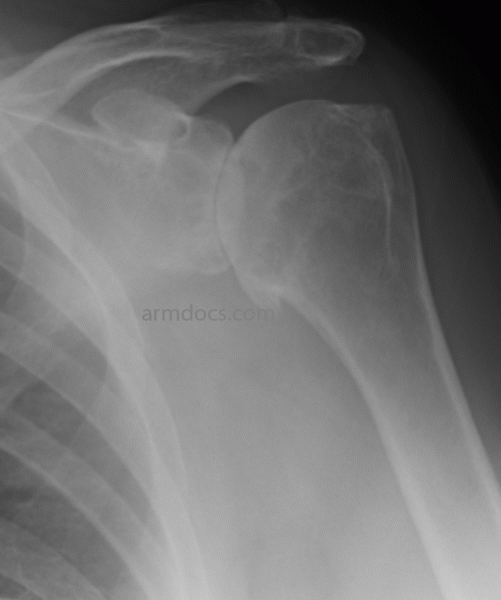

A diagnosis of shoulder arthritis is made based on the history of a gradual onset of pain in the shoulder. Pain is usually aching in nature and experienced over the front of the shoulder or near the armpit. It is often associated with stiffness in the shoulder and a feeling of roughness when moving the shoulder. Examination shows painful restriction of movements of the shoulder. An X-ray may demonstrate narrowing of the joint, erosion and formation of spurs. An ultrasound scan may be performed to examine the state of the rotator cuff. Special imaging with a CT scan or an MRI scan is sometimes necessary to aid in planning treatment.